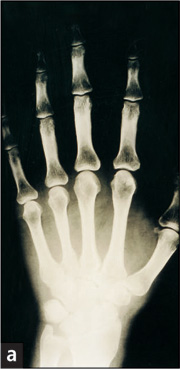

a. Röntgenbild einer rechten Hand: Nach einem Unfall lassen sich trotz starker Schmerzen keine Knochenverletzungen nachweisen. |